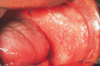

Describe the macroscopic appearance of pemphigus vulgaris.

Blisters are flaccid meaning that they rupture easily exposing a red raw surface underneath

Describe the macroscopic appearance of pemphigus foliaceus.

- You rarely see intact bullae because they are so thin and fragile

- You are likely to see some flaky remnants of old bullae